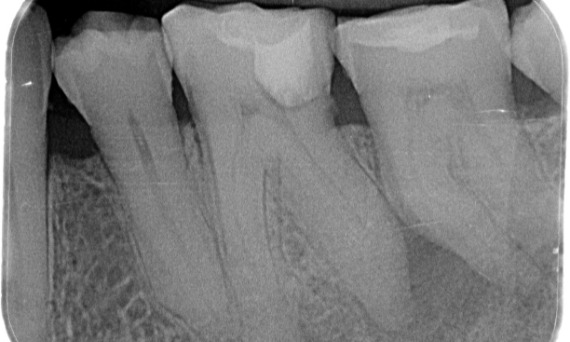

Przed: Podczas badania stwierdzono zmianę próchnicową związaną z dolnym prawym pierwszym trzonowcem. Badanie radiologiczne wykazało bliskość zmiany do rogu miazgi. Łącząc to z główną skargą pacjenta, postawiono ostateczną diagnozę przewlekłego nieodwracalnego zapalenia miazgi.

Po: Dostęp do ubytku został wykonany tak zachowawczo, jak to tylko możliwe. System TruNatomy został wybrany ze względu na młody wiek pacjenta. Musieliśmy zachować zębinę w jak największym stopniu, aby zwiększyć zdolność zęba do pokonywania obciążeń okluzyjnych i zwiększyć trwałość ostatecznej odbudowy.